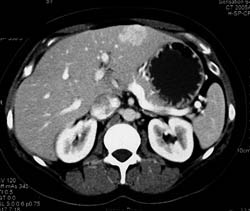

Diagnosis

Focal Nodular Hyperplasia (FNH)